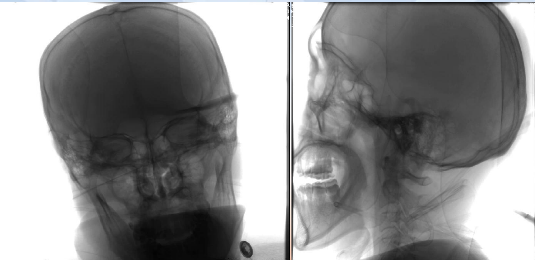

术前检查

病历夹什么径技·第152期|串联营病历夹:川陕大营_https://www.jmylbn.com_新闻资讯_第59张

病历夹什么径技·第152期|串联营病历夹:川陕大营_https://www.jmylbn.com_新闻资讯_第60张

病历夹什么径技·第152期|串联营病历夹:川陕大营_https://www.jmylbn.com_新闻资讯_第61张

<<滑动查看下一张图片>>

初步诊断:1.脑梗死(右)急性期2.右侧颈内动脉起始部次全闭塞3.右侧大脑中动脉M1段血栓形成